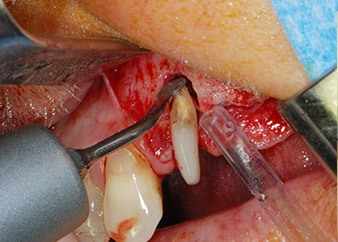

However, we maintained our initial plan to retain both teeth as temporary bridge abutments during the six-months osseointegration period of the implants. At reentry, the situation would have to be reassessed. First, in an attempt to manage the endo-perio problem, the remaining root surface was carefully debrided with piezoelectric equipment (Piezomed, W&H, used with the spatula-shaped insert S1, originally designed for erosion of the lateral sinus wall) (Fig. 4).

Then the apex was abraded with the same instrument to remove residual infected apical tissue and to reduce possible accessory root-canal ramifications (apicoectomy) (Fig. 5). A retrograde filling was not necessary because the orthograde filling had just been revised.

periodontium

Fig. 4: To preserve the tooth as a temporary abutment, the periodontium was debrided with piezoelectric equipment …

buccal apex of tooth 24

Fig 5: ... and the buccal apex of tooth 24 was abraded with the same instrument (apicoectomy).